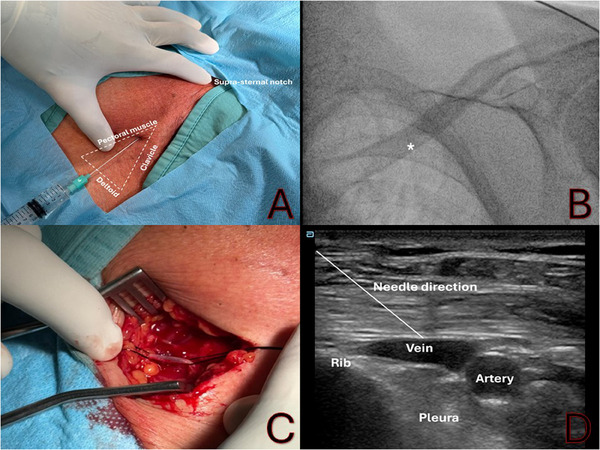

Introduction: Ultrasound (US)-guided axillary vein puncture is a safe and effective approach for cardiac implantable electronic device (CIED) implantation, and it is highly recommended by the current consensus document. However, only reports on small populations are available in the current literature regarding the comparison of this technique with other traditional approaches (subclavian vein blind puncture and cephalic vein surgical cutdown).

Purpose: We aimed to assess the effectiveness and safety of US- guided axillary vein puncture using a microintroducer kit for CIED implantation as compared to the aforementioned traditional approaches.

Methods: All consecutive patients with an indication to CIED implantation were prospectively enrolled in our observational study from March 2021 to July 2023. Patients were divided into three groups based on venous access route, according to the operator's preference: cephalic vein surgical cutdown (G1), US-guided axillary vein puncture (G2), and subclavian vein blind puncture (G3). Clinical and procedural characteristics, success and complication rates were considered for analysis.

Conclusions: US-guided axillary vein puncture for CIED implantation using a microintroducer kit is a safe technique with a very high success rate. Compared to other traditional approaches, it allows to get access with a lower number of puncture attempts and with reduced times, without prolonging the total procedural time. Moreover, x-ray use and need for contrast medium are very rare in US-guided axillary approach. Hence, it should be considered the strategy of choice for most patients undergoing CIED implantation.